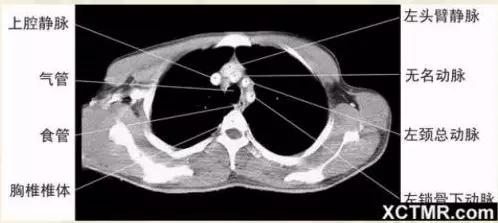

主动脉弓上层面